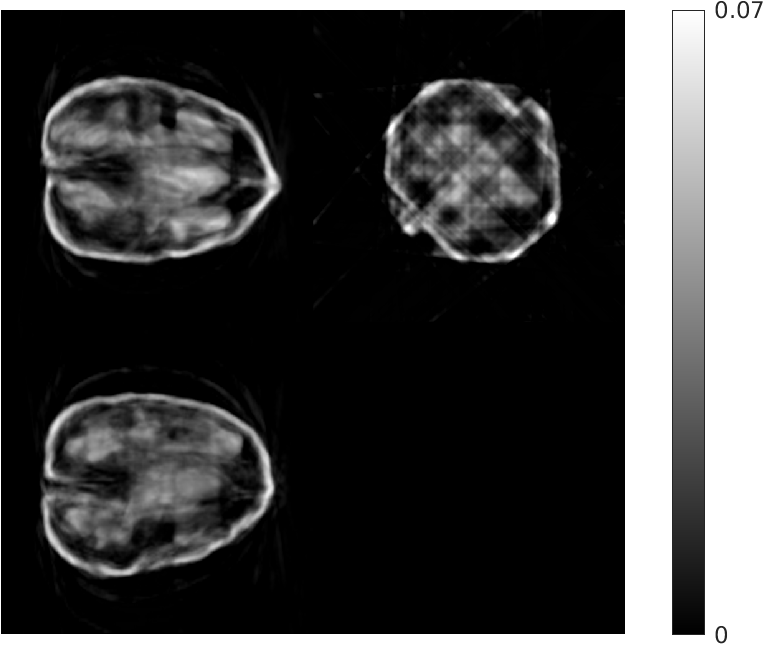

Fig. 5 shows walnut 1 from our test dataset being progressively reconstructed from 8 projections across the stages of our algorithm; as the stages progress, more features are restored in the reconstructed walnut, until the improvements become incremental. The residual streaking artifacts outside the walnut are mitigated in the reconstructions from the third and fourth stages.

| Stage 1 | Stage 2 |

![]() |

| (a) (MAE: 0.32) | (b) (MAE: 0.29) |

| Stage 3 | Stage 4 |

| (c) (MAE: 0.27) | (d) (MAE: 0.26) |